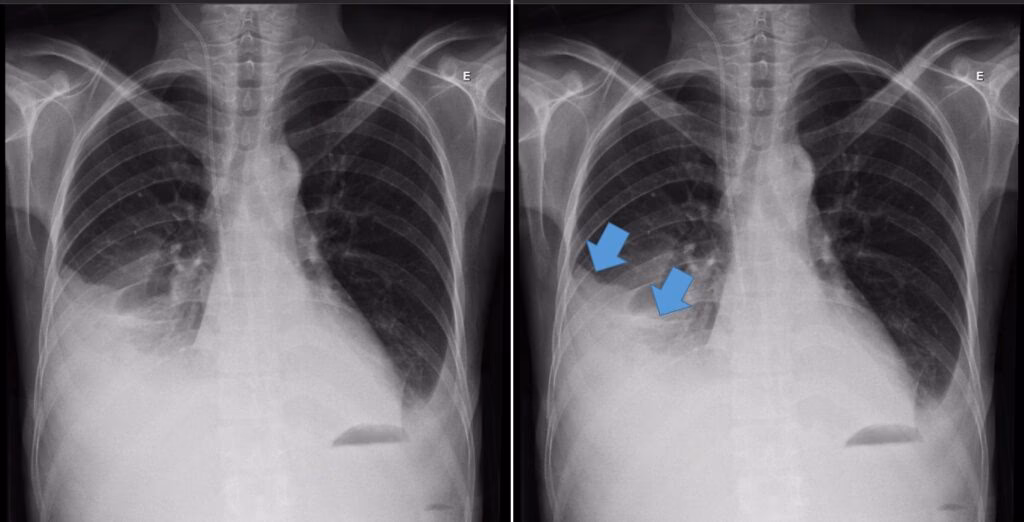

- Røntgen af thorax (brystkassen): Dette er typisk den første undersøgelse. Et røntgenbillede kan vise tegn på lungebetændelse (et infiltrat) og samtidig afsløre tilstedeværelsen af væske i pleurahulen. Et billede taget, mens patienten ligger på siden (lateral dekubitus), kan hjælpe med at vurdere mængden af væske og om den er fritflydende.